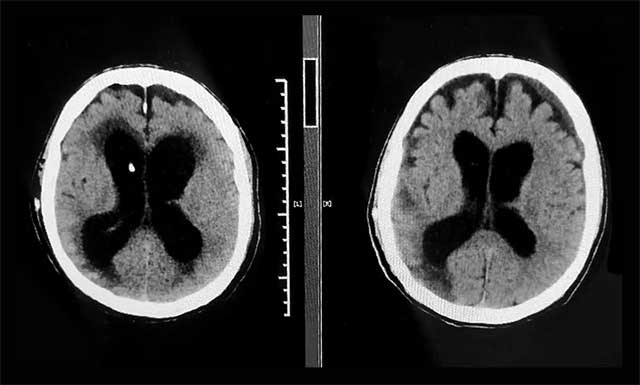

▲ 術(shù)前(左)和出院前(右)CT比對,患者原先擴(kuò)張的腦室已縮小,癥狀改善明顯

入院時(shí),汪先生神志昏迷、氣管切開無法自主呼吸、鼻飼飲食、留置尿管,可以說處于“植物人”狀態(tài)。像這樣的腦出血昏迷患者,病情隨時(shí)可能惡化,張琪博士團(tuán)隊(duì)為患者完善相關(guān)檢查,結(jié)合既往病史,多次開展病情討論評估,制定了有針對性的治療方案。鑒于患者有中度腦積水,嚴(yán)重影響意識恢復(fù),張琪博士親自為患者進(jìn)行了腦室-腹腔分流手術(shù)。